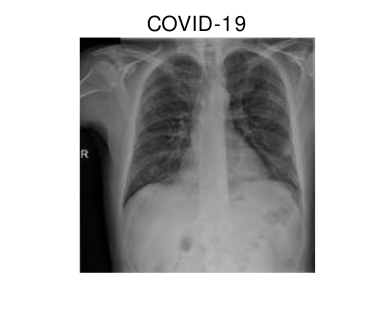

In hospitals, chest X-rays can mitigate these drawbacks by enabling a fast and reliable diagnosis. Figure 1 shows chest X-ray scans of healthy (top) and COVID-19 (bottom) patients in direct comparison. Even though patchy consolidations are recognizable in the COVID-19 scans, such X-rays remain challenging to interpret. Specialists, however, are able to identify the severity of a case early on and can take measures without waiting for lab results.